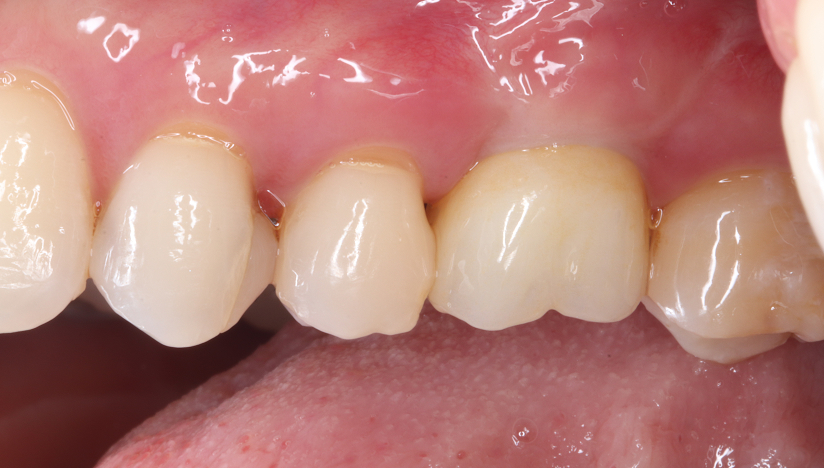

インプラントの症例紹介

臼歯部(奥歯)の

インプラント治療

タップで写真の拡大ができます。

Before

After

主訴

噛むと痛い、歯茎が腫れてきた

治療内容

抜歯即時インプラント埋入、リッジプリザベーション(顎堤温存術)

治療期間

6〜8ヶ月

治療費用

649,000

治療の

リスク

オッセオインテグレーションが得られなかった場合、撤去、再度埋入の可能性